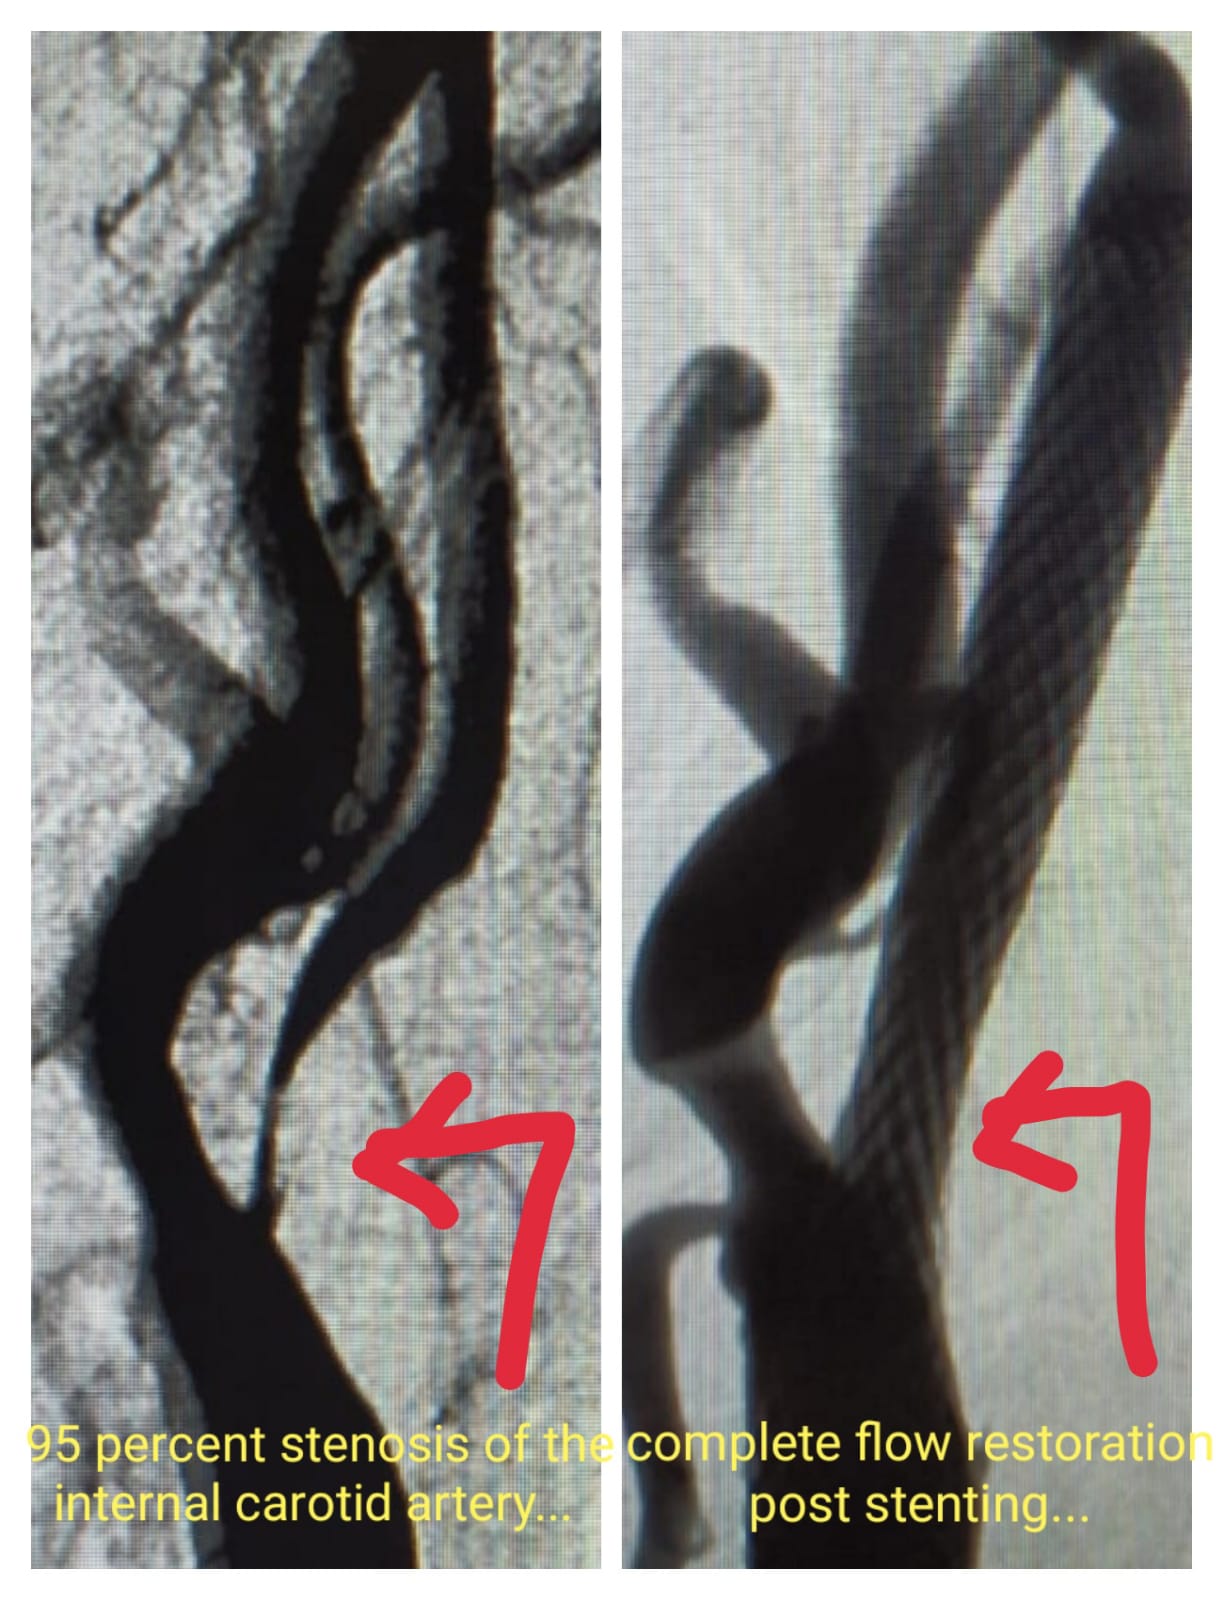

Carotid Artery Stenting Procedure Pre procedure - 95% stenosis in Internal Carotid Artery Post Procedure- Deploy Stent & restore complete blood flow